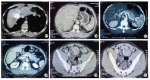

Case report: We describe a clinical case, he was diagnosed with HCC a year ago, treated with TACE (transarterialchemoembolisation), re-examined with abdominal pain and defecation disorder. The tests such as CT scan, colorectal endoscopy, fine needle aspiration (FNA) revealed secondary metastatic lesion of HCC in sigmoid colon. This is the first gastrointestinal (GI) tract metastatic we have encountered.